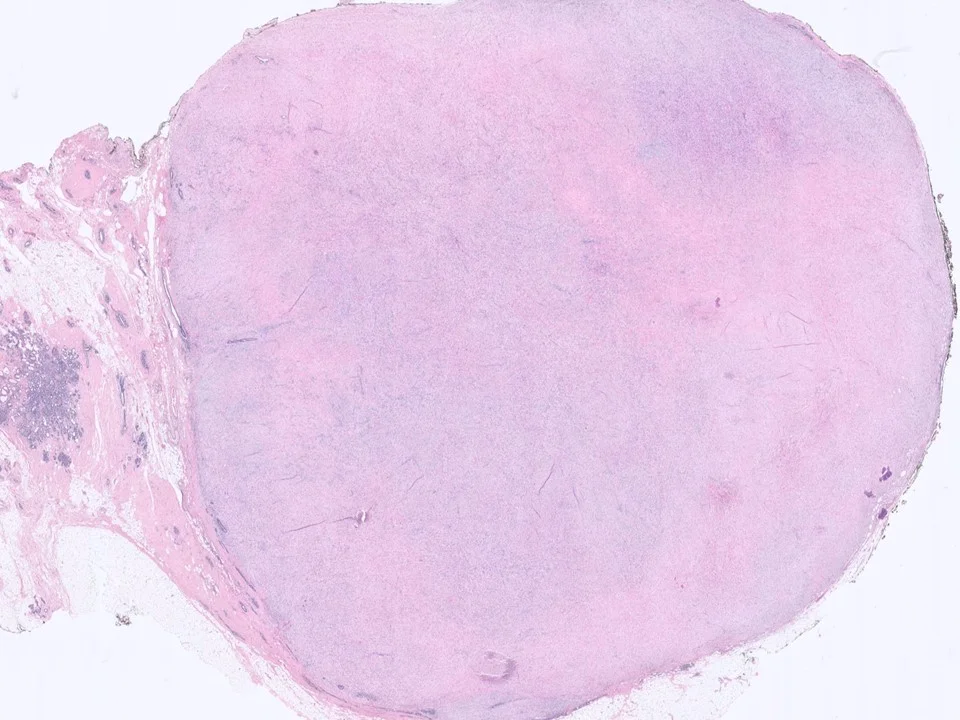

Fibroadenoma

Fibroadenomas are the most common benign tumors of the female breast. They are predominantly found in young women (under age 30), present as solitary, palpable, firm, mobile mass, and are usually <3 cm in size. Grossly, they have a tan-grey, bulging, lobulated cut surface, often with visible slit-like spaces.

On histological examination, fibroadenomas are well-circumscribed and characterized by a proliferation of both stromal and glandular elements. Two growth patterns are recognized: intracanalicular and pericanalicular. The epithelium may show a variety of alterations, including metaplastic changes (esp apocrine), cystic change, and sclerosing adenosis, as well as epithelial proliferative changes (UDH, ADH, ALH, LCIS, and DCIS). Invasive carcinoma may also involve FAs.